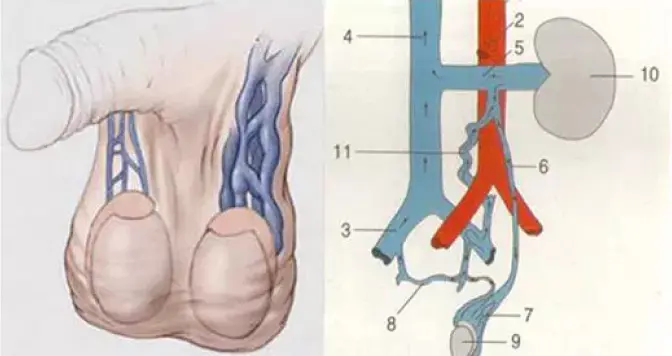

سب کچھ آسان ہے: پروسٹیٹ میں سیمینل سیال پیدا ہوتا ہے، اور نئے سیال کے لیے جگہ بنانے کے لیے اسے وقتاً فوقتاً چھوڑا جانا چاہیے۔ لیکن اگر آدمی نامرد ہو جائے تو اس کے اندر کی رطوبت رک جاتی ہے۔ یہ بنیادی طور پر پروٹین پر مشتمل ہوتا ہے، اور وقت کے ساتھ ساتھ یہ سڑے ہوئے انڈے کی طرح گلنا شروع ہو جاتا ہے۔

پیتھوجینک مائکروجنزم اور بیکٹیریا پروسٹیٹ میں بڑھ جاتے ہیں۔ بیکٹیریل پروسٹیٹائٹس تیار ہوتا ہے۔ غدود کے ؤتکوں میں ناقابل واپسی تبدیلیاں واقع ہوتی ہیں۔ یہ پروسٹیٹ اڈینوما کی طرف جاتا ہے - ایک سومی تشکیل (پیتھوجین کی موجودگی کی وجہ سے، خلیات ناکافی طور پر تقسیم ہونے لگتے ہیں)۔

انسان میں عضو تناسل کے حصول کا عمل دو مراحل پر مشتمل ہوتا ہے۔ پہلا مرحلہ جنسی جذبہ ہے۔ دوسرا عضو تناسل کے غار دار جسموں کو خون سے بھرنا ہے۔ Prolan دونوں مراحل کو ایک ساتھ متاثر کرتا ہے۔ نتیجے کے طور پر، ایک پائیدار کھڑا آدمی کو واپس آتا ہے.

عضو تناسل میں ہائی بلڈ پریشر

عضو تناسل کے حجم اور سختی میں اضافہ غار کے جسموں کو خون سے بھرنے کے نتیجے میں ہوتا ہے۔ Prolan یہ کیلشیم چینلز کو صاف کرتا ہے اور ایشیوکورنوس پٹھوں کی بڑھوتری کو بڑھاتا ہے، اس طرح تحریک کو بہتر بناتا ہے۔ ایک آدمی کو مضبوط عضو تناسل کا تجربہ ہوتا ہے، اس کے ساتھ جنسی جوش بھی ہوتا ہے۔